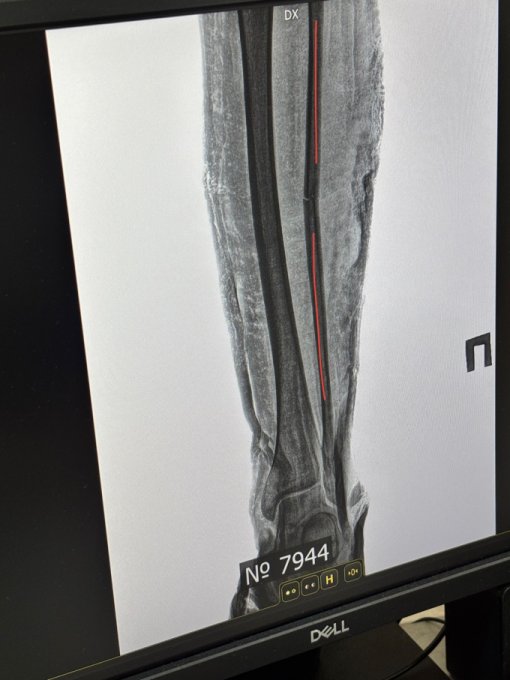

Сломала я ногу на скалодроме. Косяк мой, просто приземлилась неправильно, я уже давно лазаю, но как говорится, никто не застрахован от таких неприятностей. Так что начинаю свой период восстановления спустя 10 дней с момента перелома. Очень сложно взять себя в руки и смириться со своей временной малоподвижностью, а так же невозможностью сходить самостоятельно в магазин. Ну да ладно! Стараюсь не унывать)

Вчера два часа рыдала от того, что кость может срастись криво, но врачи говорят что это ок… Я конечно не эксперт в травматологии, но вроде бы оно не совсем ровненько идет. Я понимаю, что может для обычной жизни это норм, но я постоянно занимаюсь спортом. Я не хочу, чтобы в самый неподходящий момент эта малютка подвела меня и сломалась просто потому что чуть чуть кривенько срослась…

наверное из-за перелома у меня появилось свободное время, которое я трачу на обдумывание собственной жизни. Своей значимости в этом мире. Поиском своих желаний по жизни. Ну и закончу свое непонятное рассуждение забавный картинкой из мультсериала.